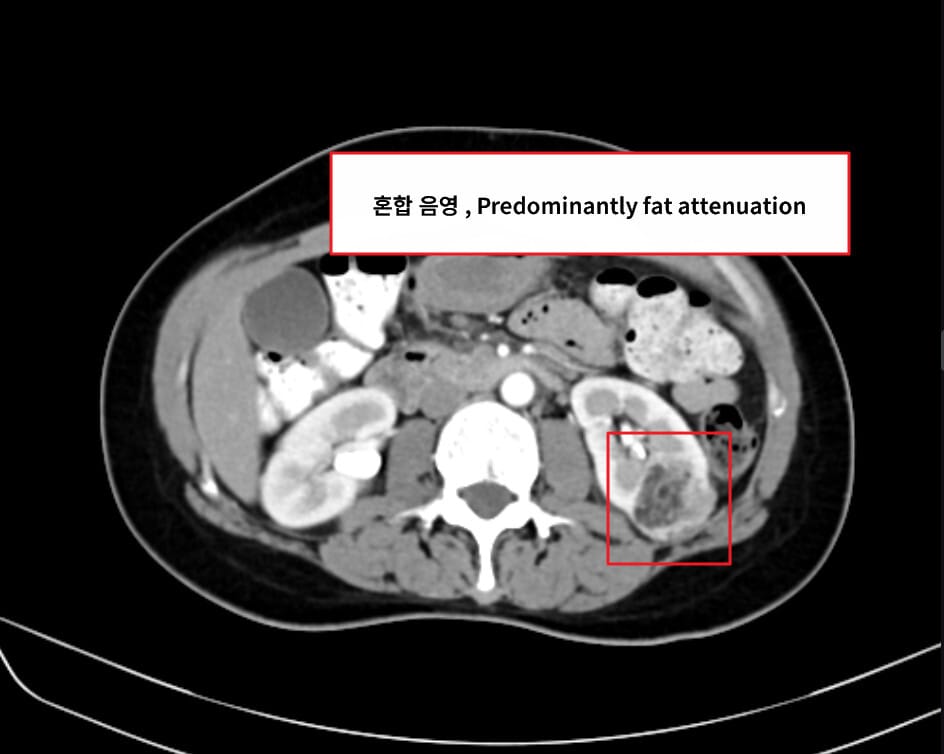

[진단]

– CT/MRI에서 지방 성분(−HU) 확인

Renal Cell Carcinoma와 감별

–Overflowing beer sign

신장 변연부에 돌출된 병변이 맞닿는 면적이 3mm 이상이면 Renal cell carcinoma 보다 Fat poor angiomyolipoma를 시사합니다.